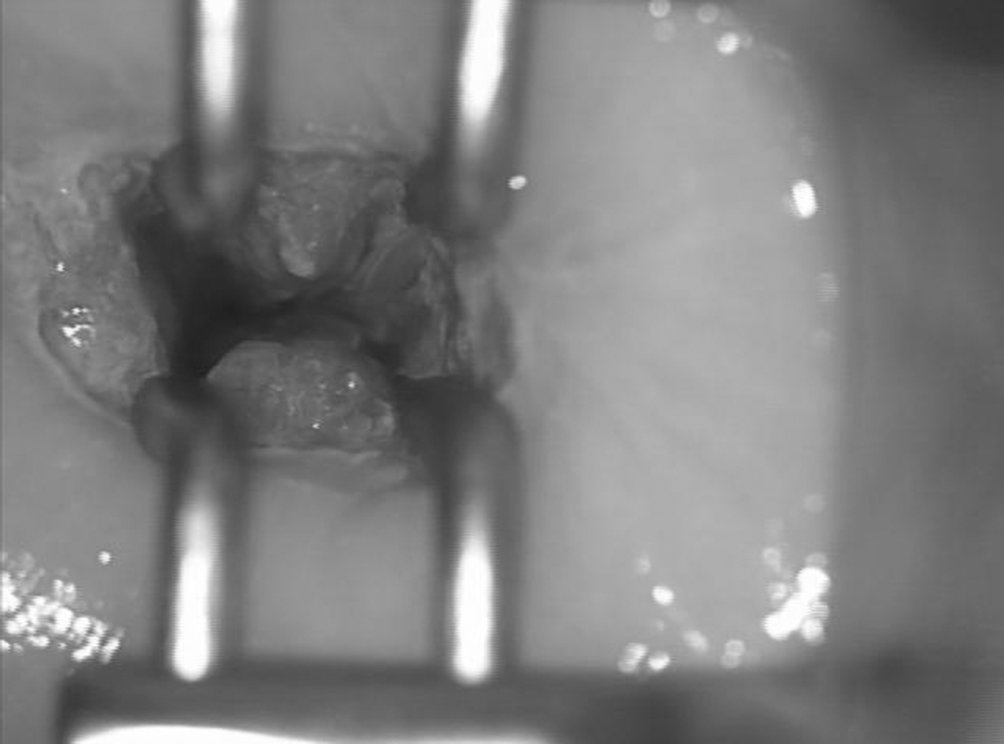

Figure 18.3 Visualisation de la jonction squamo-cylindrique endocervicale à l’aide d’un spéculum endocervical de Koogan.